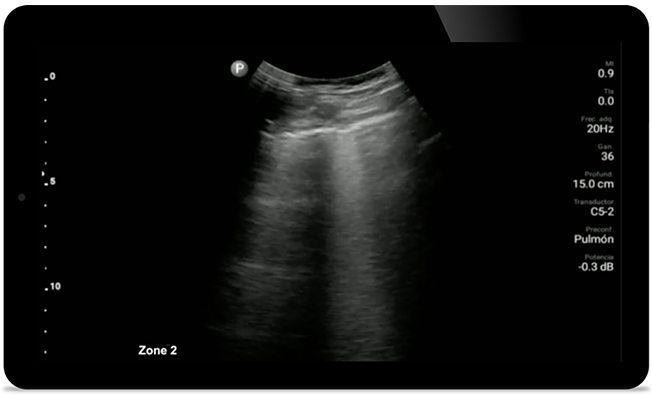

Keep an eye on COVID pneumonia

Lumify can help give results similar to a chest CT when evaluating pneumonia and adult respiratory distress syndrome.